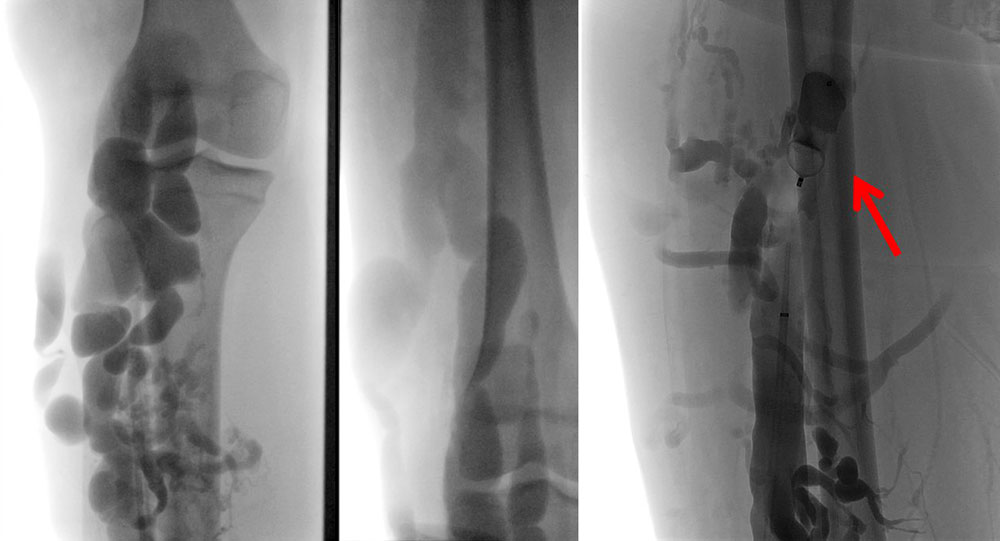

• Closure of the connection of the communicating or drainage veins from the tubular (e.g. marginal vein) or spongiform (e.g. large intramuscular) venous malformation to the draining venous system. This can be done either by minimally invasive methods (e.g., using platinum coils, Amplatzer vascular plugs, radiofrequency ablation, alcohol gel) or by open surgery using ligation and, if necessary, resection.